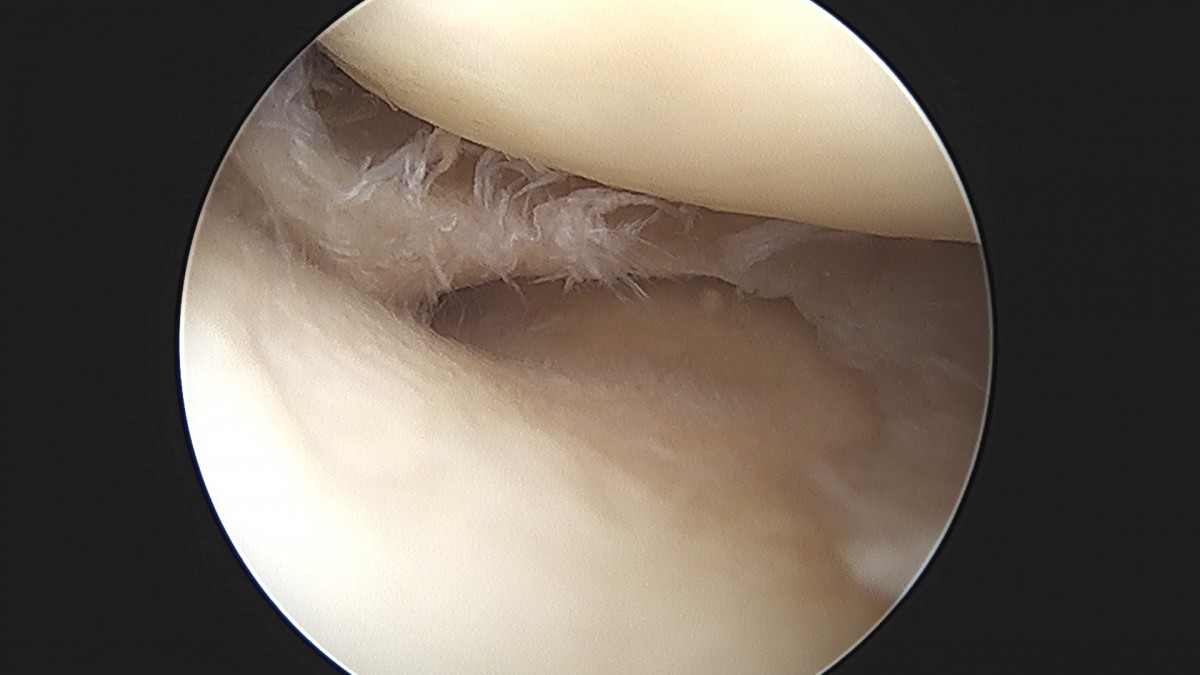

이재상원장님 무릎 반월상 연골판 절제술 김민O 환자

작성자 최고관리자 댓글 0건 조회 365회 작성일 25-09-16 16:10